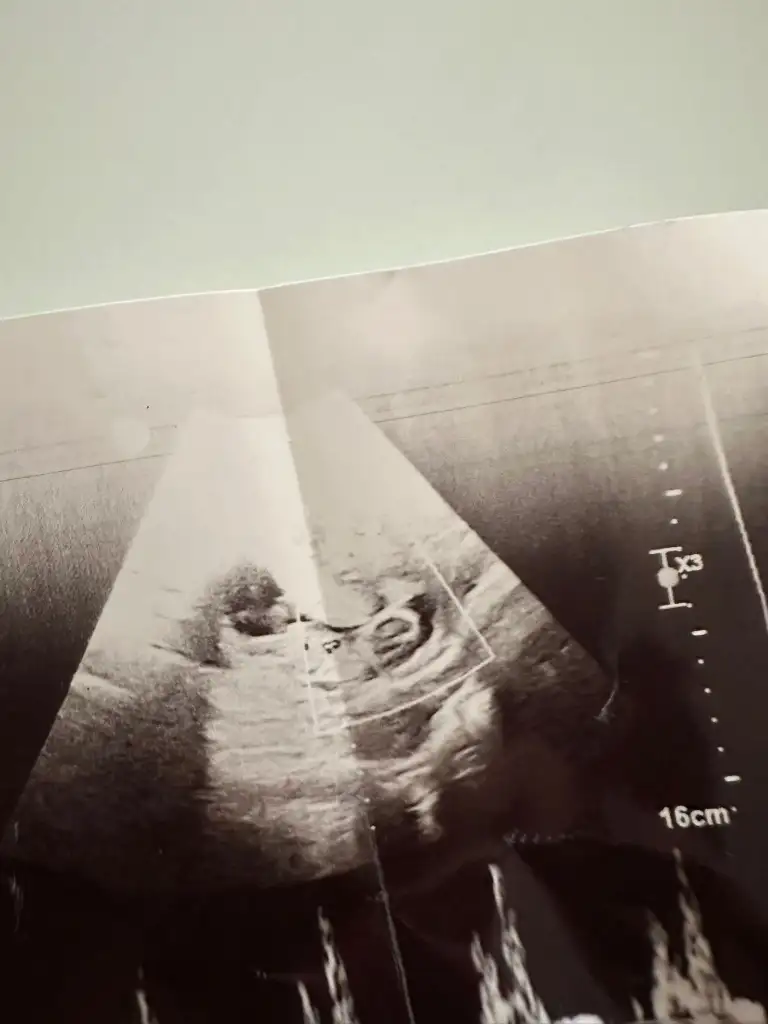

13 haftalik bakarmisiniz nedir sizce

Çok merak ediyorum, karından bakıldı bu arada